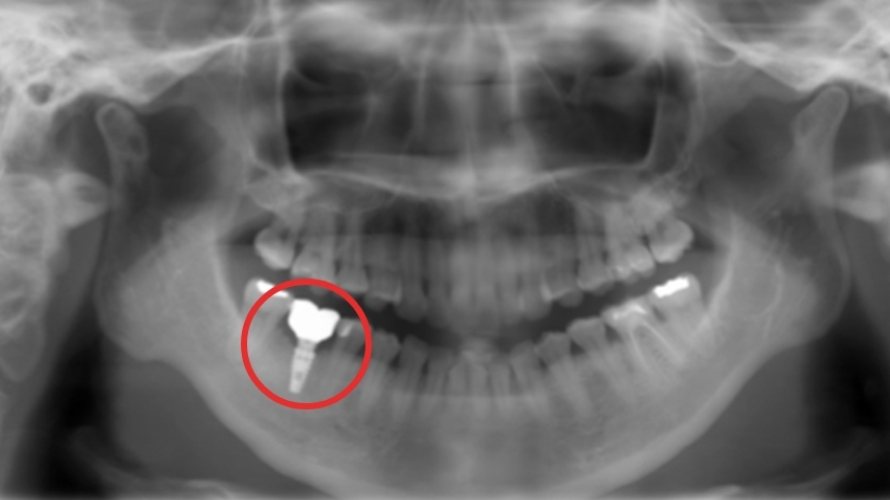

Bさん

通院先ではインプラント手術を受けられない方

治療のために抜歯するも、通っていた歯科医院ではインプラントを取り扱っていませんでした。インプラントができると知り合いから紹介されて、川越歯科医院に行きました。

治療概要

| ご希望 | 抜歯した後、放置していた左下奥歯に歯を入れたい。 |

|---|---|

| 治療内容 | 抜歯後からおよそ6年経過し頬側が吸収したため、インプラントを埋入及び頬側GBR(歯槽骨を再生する治療)。 |

| 治療期間・回数 | 4ヶ月・5~7回 |

| 費用 | 41万円 〜 44万円 |

| 想定されるリスクと副作用 | 1~2週間の痛み、腫れ、内出血。 |

上部構造装着後のレントゲンと口腔内写真

手術を終えて

他院で抜歯から時間が経っていたので不安なまま過ごしていました。今は、大好きなホルモンを美味しく感じられて幸せです。

先生から一言

抜歯から6年経過しており、インプラントを入れるには骨が減っていましたが“インプラントを入れたい”という患者様のご希望に沿うことができました。お肉屋さんを経営されているので、これからより一層大好きなお肉をしっかり咬んで楽しんでいただけたらと思います。